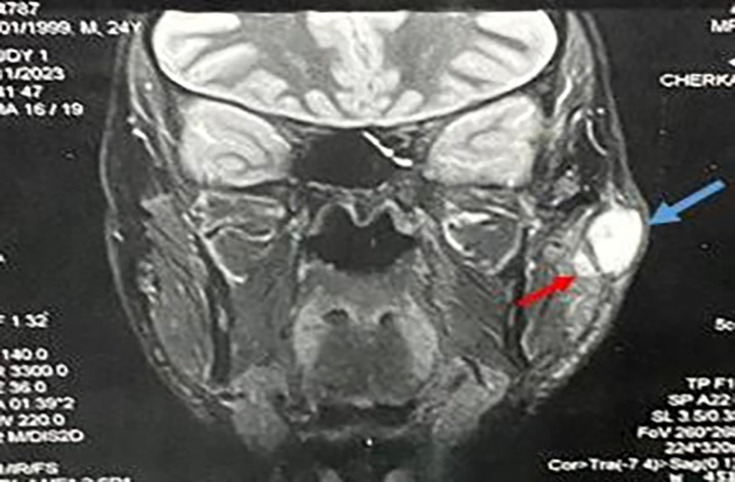

Extrapulmonary tuberculosis often presents as lymphadenitis. In the head and neck area, tuberculous involvement of the parotid gland is rare and challenging to diagnose due to non-specific symptoms, which can be confused with a tumour. Tuberculous conjunctivitis, although uncommon, should be considered in cases of chronic, treatment-resistant conjunctivitis. The association of primary parotid and conjunctival tuberculosis is exceptional. They are difficult to diagnose due to the non-specificity of their clinical, biological and radiological signs. We report the case of a 24-year-old immunocompetent patient with no history of tuberculosis, who presented with intermittent swelling of the left parotid gland, accompanied by unilateral redness of the eye, which appeared 2 months later, in a context of fever and night sweats. The patient also reported a foreign body sensation in his eye, mild tearing and photophobia. Clinical examination revealed painful, warm swelling of the left parotid gland, as well as localized granulomatous conjunctivitis. Cervico-parotid CT and MRI revealed two well-limited, oval, left parotid formations with a slightly thickened and enhanced wall after injection of gadolinium, suggestive a priori of abscessed collections. The diagnosis of primary parotid and conjunctival tuberculosis was made on the basis of histological examination of the biopsies, as well as direct examination, culture and GeneXpert. The patient progressed well on anti-bacillary treatment. Our work underlines the great importance of GeneXpert, which is a rapid and highly sensitive technique, effective in the diagnosis of extrapulmonary tuberculosis.